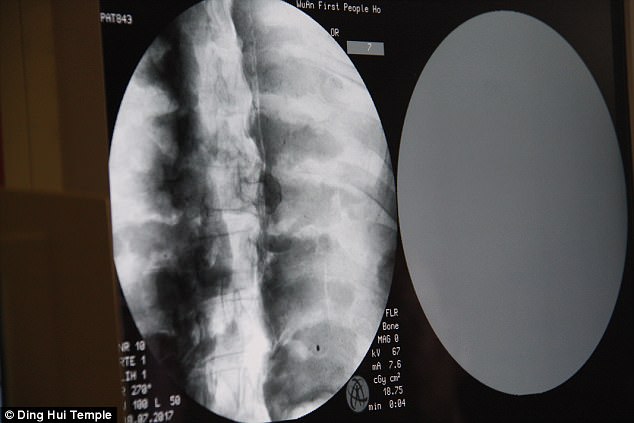

Ngày 8/7/2017, trước sự chứng kiến của các nhà sư, giới truyền thông và nhiều người dân, các nhà khoa học đã tiến hành chụp CT xác ướp nhà sư Ci Xian.

Ban quản lý của ngôi chùa đã sắp xếp một buổi chụp CT xác ướp nhà sư Ci Xian vào ngày 8 tháng 7 năm 2017.

Mọi người đều bàng hoàng khi các bác sĩ cho biết nhà sư Ci Xian vẫn còn nguyên bộ xương, và một bộ não hoàn chỉnh. Tức xác ướp này đã được bảo quản gần như nguyên vẹn sau hơn 1.000 năm. Điều này khiến giới khoa học sửng sốt với kỹ thuật ướp xác thời bấy giờ.

Bác sĩ Wu Yongqing nói với kênh Pear Video sau khi tiến hành chụp CT cho xác ướp: "Chúng tôi có thể thấy xương của ngài ấy khỏe mạnh như một người bình thường. Hàm trên, răng trên, xương sườn, xương sống và tất cả các khớp đều vẫn nguyên vẹn. Thật không thể tin được khi thấy điều này".